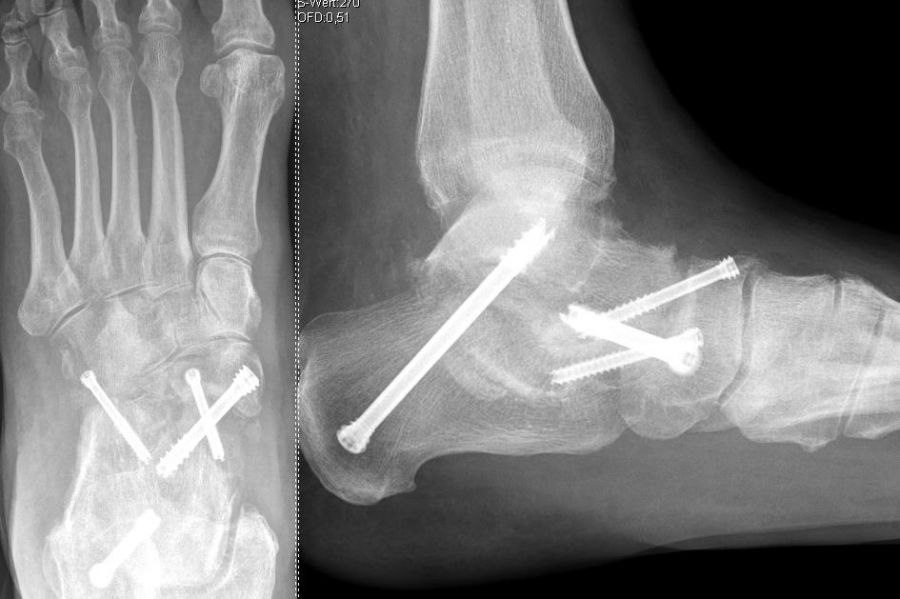

Die isolierte Arthrose der Bona Jäger Gelenkreihe (navikulocuneiforme Gelenk) ist selten und oft posttraumatisch. Meistens geht die navikulocuneiforme Arthrose mit einem schmerzhaften Pes planovalgus einher 2425. Letztlich werden die betroffenen Gelenkflächen angefrischt und mittels verschiedener Implantat-Möglichkeiten (s.o.) fusioniert. Bei gleichzeitiger Plattfußfehlstellung sollte diese ebenfalls adressiert werden 26 (Abb. 4). Ziel ist die Arthrodese in anatomischer Stellung der Gelenke.

Die Operation erfolgt meist über einen medialen Zugang. Nach Entknorpeln der  Gelenkflächen und Anfrischen des subchondralen Knochens kann die Arthrodese mit Schrauben oder Plattensystem erfolgen (Abb. 5). Bei Fehlstellungen muss diese vor der Osteosynthese korrigiert und das Talonavikulargelenk reponiert werden. Pseuarthrosen werden hier zwischen 8-25% angegeben 3223.

Die Calcaneocuboidal-Arthrodese ist meistens Teil weiterer Arthrodesen im Bereich der Fußwurzel 34 (Abb. 10).  Eine besondere Bedeutung kommt der Calcaneocuboidal-Arthrodese bei Eingriffen zur Behandlung des Plattfußes, die der Verlängerung der lateralen Säule dienen, zu 35. Die Arthrodese kann mittels Schrauben, Klammern, Plattensystemen und ggf. der Interposition eines kortikospongiösen Spanes zur Verlängerung der lateralen Säule erfolgen.